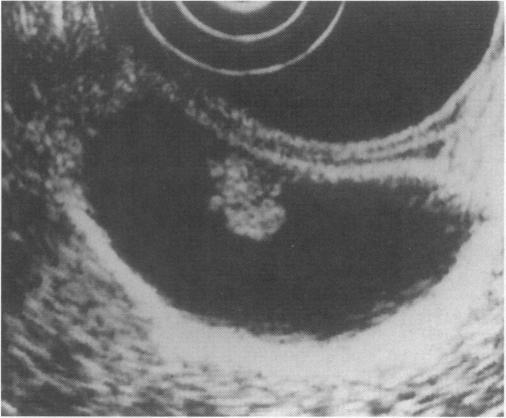

Polypoid lesions exceeding 10 mm suggested malignancy. EUS showed a tiny echogenic spot or an aggregation of echogenic spots with or without echopenic areas in 95% of patients with cholesterol polyps. EUS showed multiple microcysts or comet tail artifact in all adenomyomatosis cases. Adenomas and adenocarcinomas were not associated with the echogenic spots, microcysts, or artifacts. Among adenomas and adenocarcinomas, all sessile lesions were adenocarcinomas. EUS differentiated among polypoid lesions more precisely than ultrasonography (97% vs. 71%).

A tiny echogenic spot or an aggregation of echogenic spots and multiple microcysts or comet tail artifact is pathognomonic for cholesterol polyp and adenomyomatosis, respectively. Polypoid lesions without these findings indicate adenoma or adenocarcinoma on EUS. Routine use of EUS is recommended for differential diagnosis of polypoid gallbladder lesions when ultrasonography shows no signs indicative of either cholesterol polyp or adenomyomatosis.